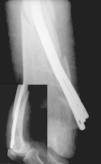

Estos dos sistemas abogan por síntesis rígidas, desechando la idea propuesta por Ender 5 , donde la elasticidad de la síntesis endomedular, asociada a la orientación en las tres direcciones del espacio dentro de la cabeza femoral, conseguía la estabilización y consolidación de estas fracturas (fig. 1).

Figura 1. Correcta posición en la cabeza femoral de los clavos de Ender en una fractura pertrocantérea.